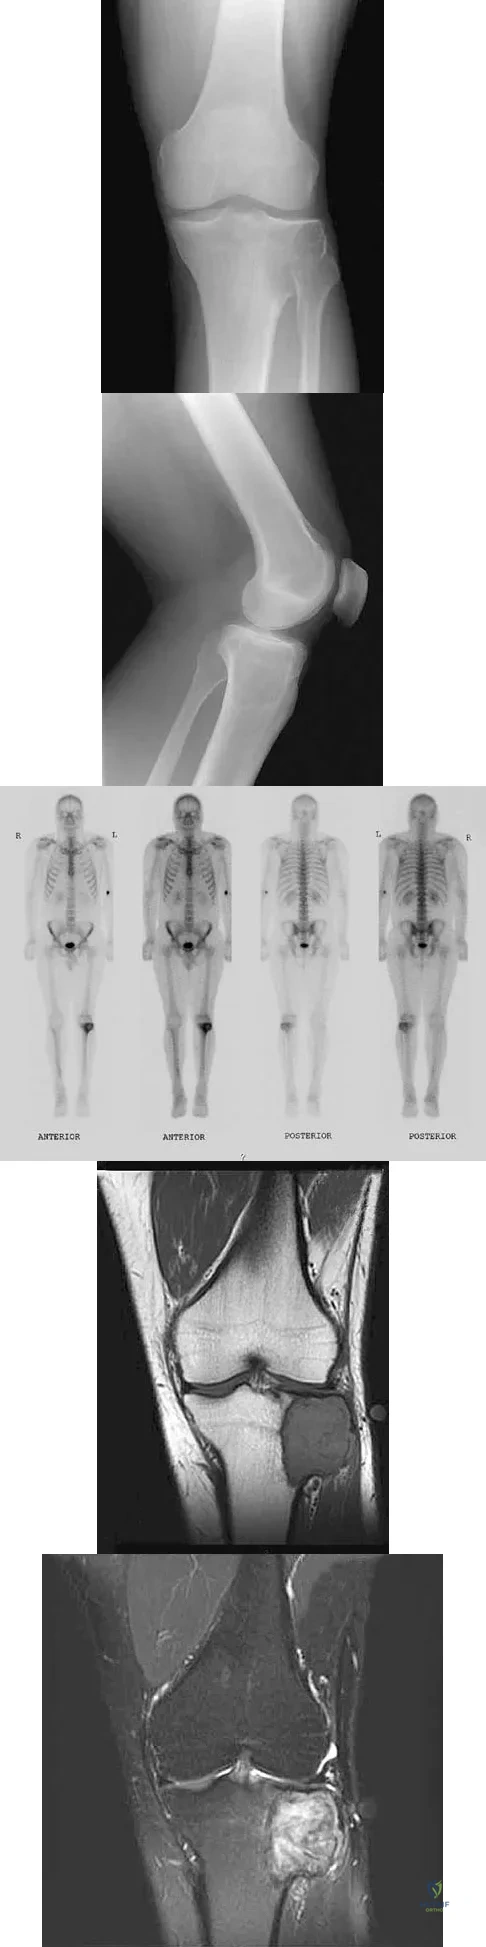

A 24-year-old man has had pain in the left knee for the past several months. He reports that initially the pain was associated with weight-bearing activities, but it has now become more constant. He denies any swelling but reports a lateral fullness at the tibial plateau. Figures 23a through 23e show radiographs, a bone scan, and T1- and T2-weighted MRI scans. What is the most likely diagnosis?

Explanation